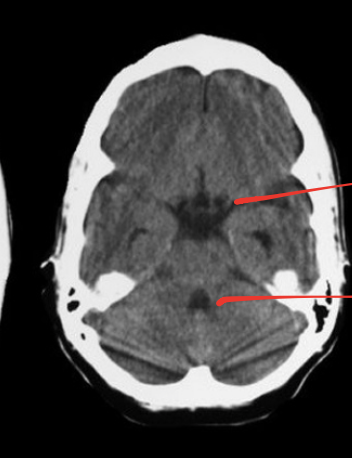

what is red dot? why is it squashed

3rd ventricles, due to the thalamus on either side!

4th ventricle _smaller_ than 3rd>> u can tell there is a blockage in aqueduct